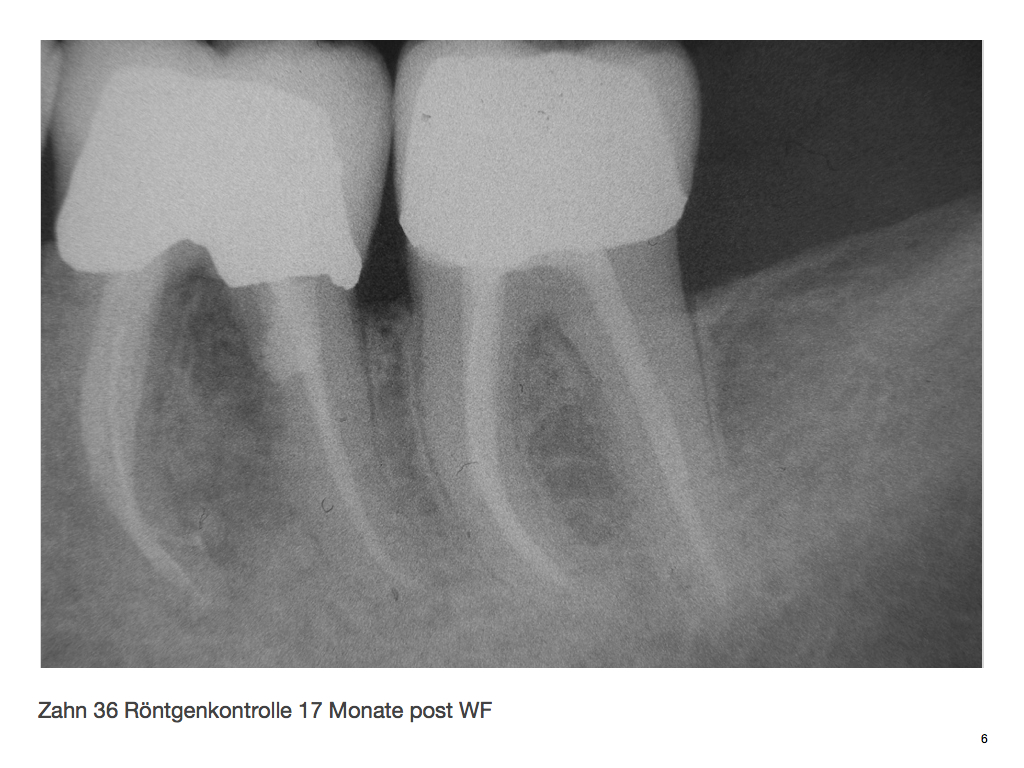

DMAWFR.006 Veröffentlicht 27. Februar 2012 am 1024 × 768 in Die Mutter aller WF – Revisionen – Recall nach 5,5 Jahren